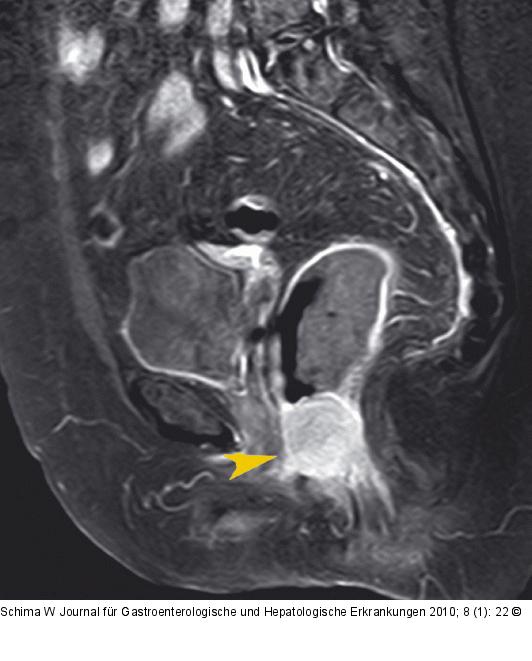

Abbildung 1c: Rektumkarzinom Die Gadolinium-verstärkte MRT zeigt gut den kontrastmittelaufnehmenden Tumor (Pfeilspitze). |

Die Gadolinium-verstärkte MRT zeigt gut den kontrastmittelaufnehmenden Tumor (Pfeilspitze). |